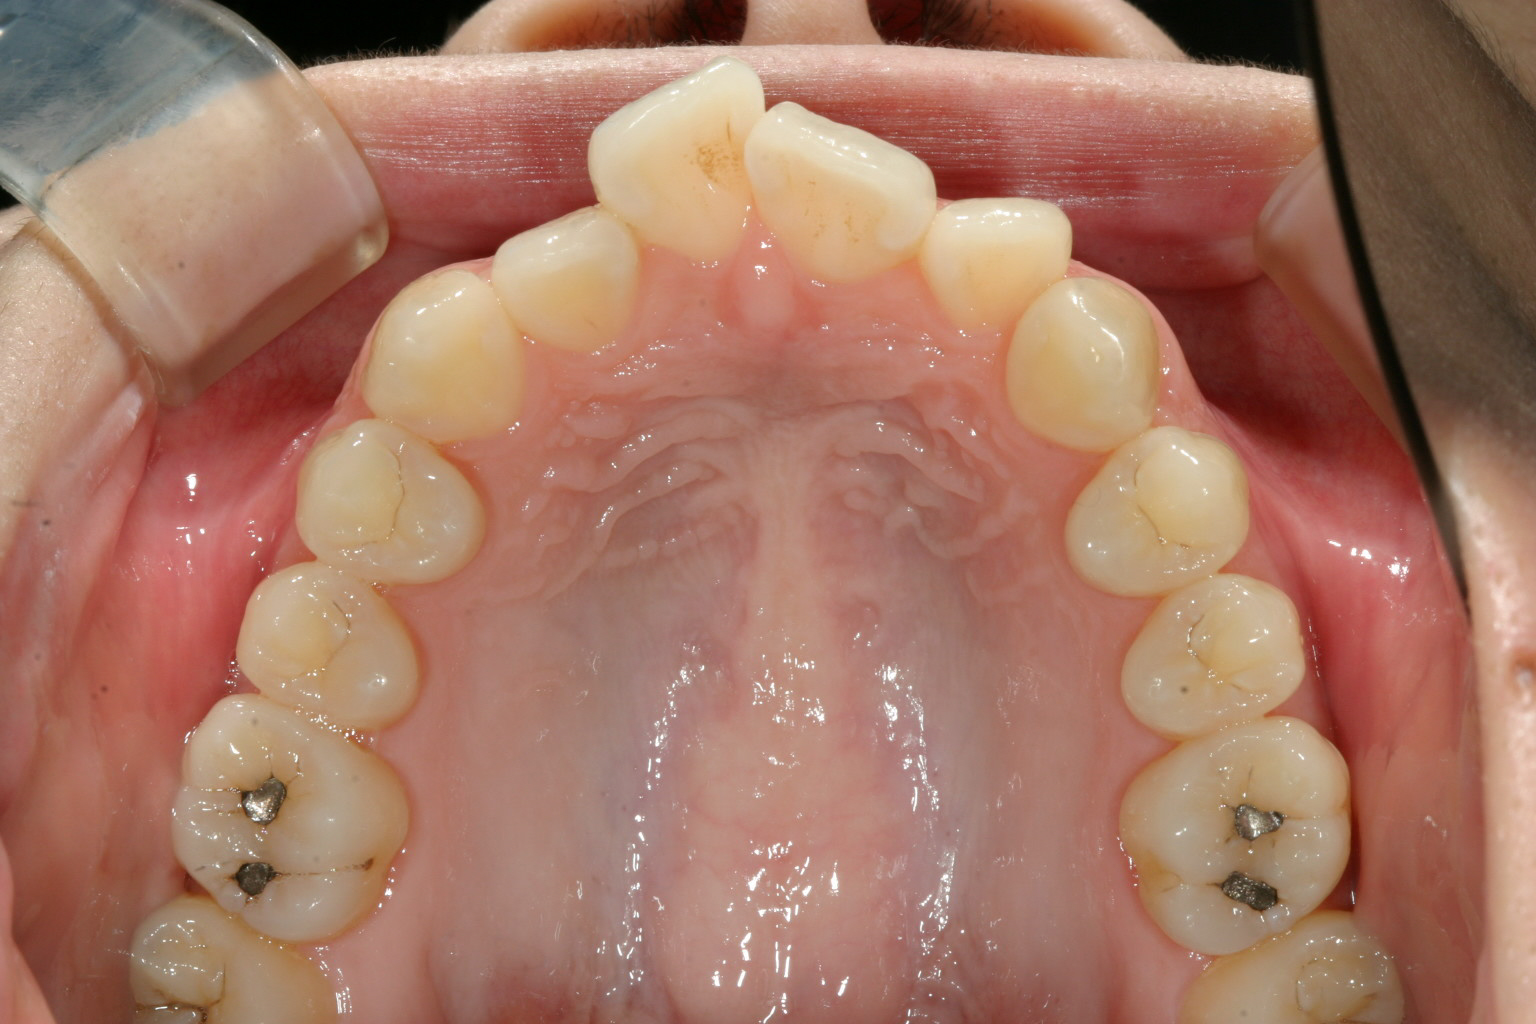

アーチがV字型な為に前歯が上手く並ばずガタガタしています。

上顎のアーチをU字に変えて綺麗に配列しました。

今回のケースは上下のアーチフォームがV字になっていた為前歯が上手く並ばず

ガタガタしていました。

この様なケースは当院の症例紹介でも頻繁に出て来るケースです。

全体的なアーチフォームをU字に改善するだけで問題は改善します。

この様な処置はインビザライン治療では得意な処置です。